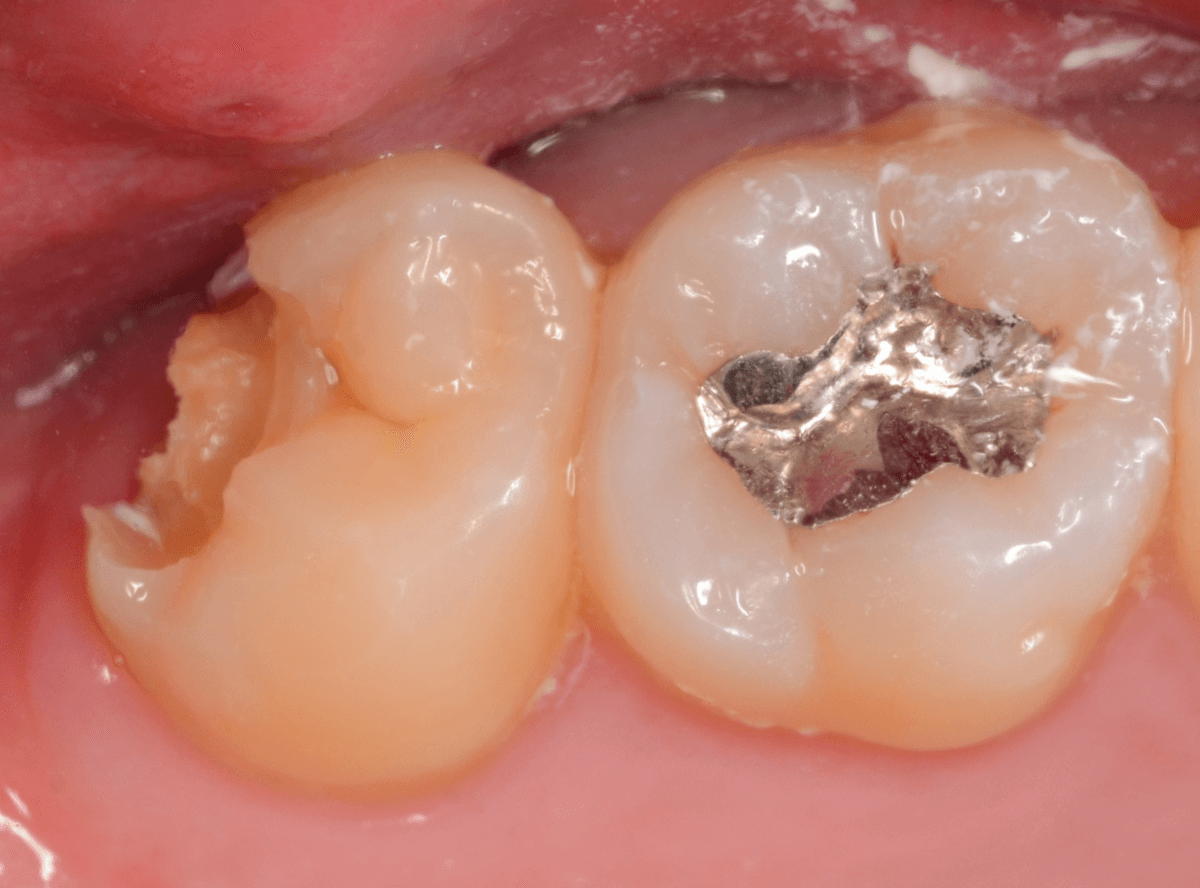

金属を外したところです。

写真では写ってしませんが、この奥に虫歯があります。

全ての虫歯を除去したところです。

抜歯した後ろのおやしらずは、元々虫歯の治療がしてありましたが、その際に抜歯しておいた方が良かったのではないかな、と思いました。